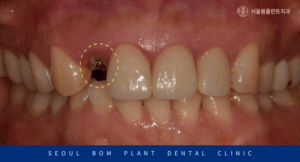

먼저 남아있는 충치 부위를

깔끔하게 제거하고 정리했습니다.

환자분과 같이 치질이

얼마 남아 있지 않은 경우에는 치아 뿌리에

Post라는 기둥을 심어 Core로

치아머리 부분을 보강해 주는

Post core를 진행하여 구조를

보강해 주는 것이 예후에 좋습니다.